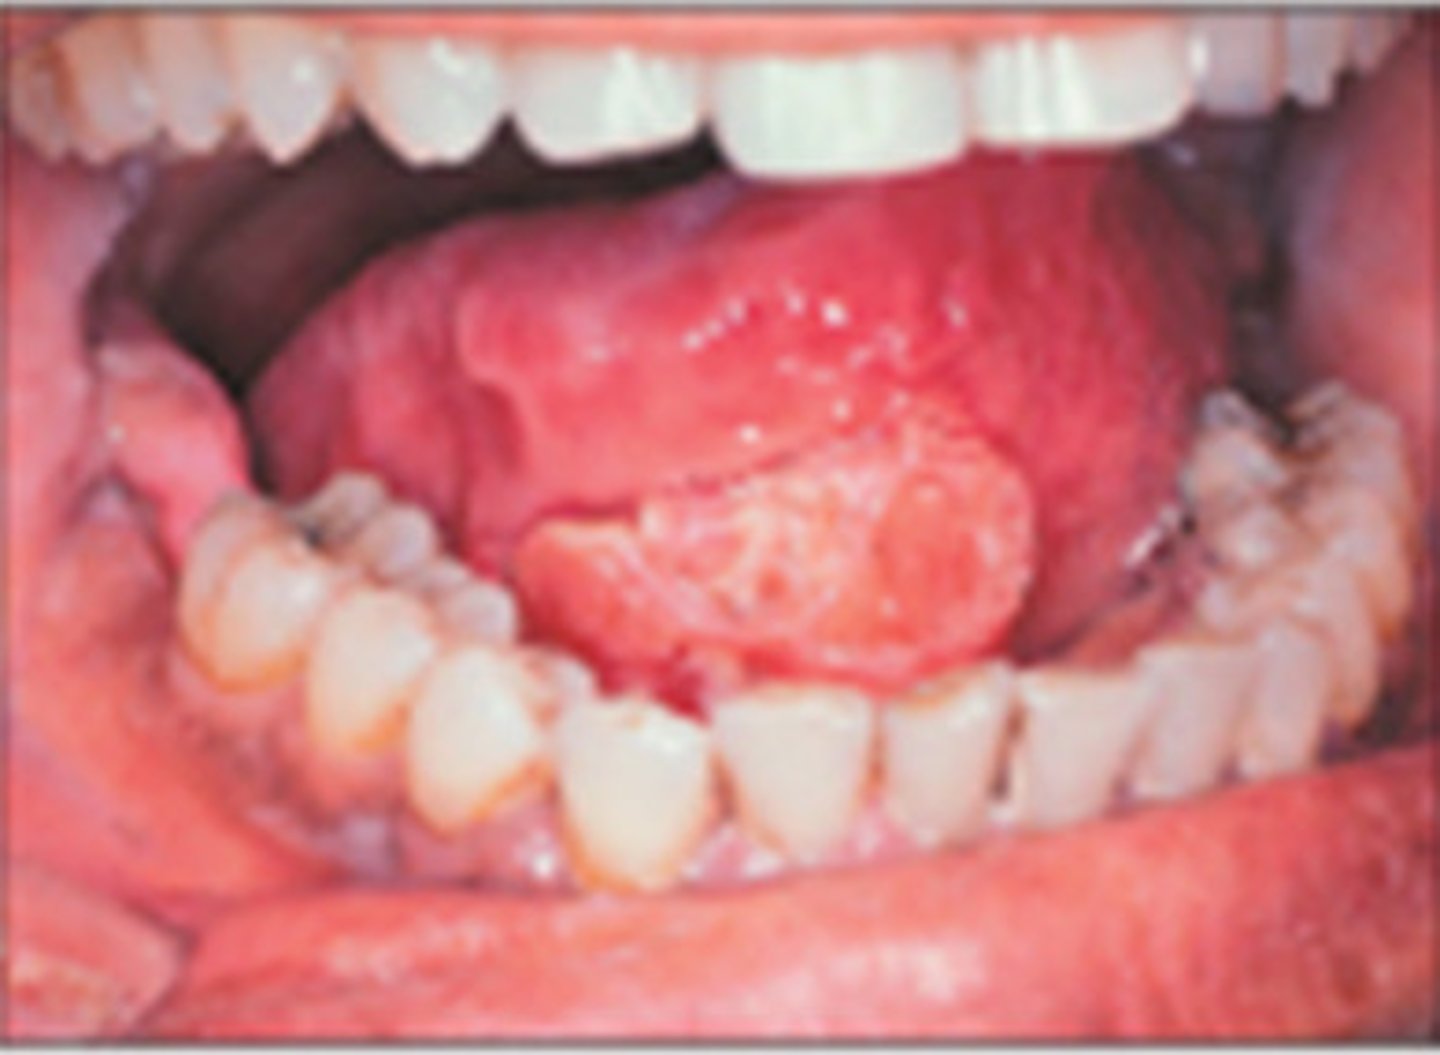

What is oral SCC? (+ high risk sites, population)

irregular shaped white patch with rolled, indurated border

⢠high risk sites: 1) tongue - most common, 2) floor of mouth, 3) tonsillar pillar/soft palate, 4) lower lip

⢠population: males over 40

⢠NON-HEALING ulcer